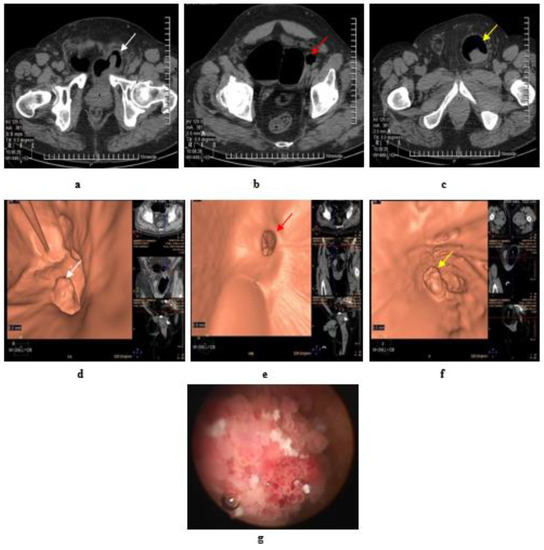

4. Intradiverticular Carcinoma

5. Ureterocele Urothelial Carcinoma

- Melekos, M.D.; Asbach, H.W.; Barbalias, G.A. Vesical diverticula: Etiology, diagnosis, tumorigenesis, and treatment. Analysis of 74 cases. Urology 1987, 30, 453–457. [Google Scholar] [CrossRef]

- Haecker, A.; Riedasch, G.; Langbein, S.; Alken, P.; Michel, M.S. Diverticular carcinoma of the urinary bladder: Diagnosis and treatment problems. A case report. Med. Princ. Pract. 2005, 14, 121–124. [Google Scholar] [CrossRef]

- Matta, E.J.; Kenney, A.J.; Barre, G.M.; Vanlangendonck, R.M., Jr. Best cases from the AFIP: Intradiverticular bladder carcinoma. Radiographics 2005, 25, 1397–1403. [Google Scholar] [CrossRef]

- Carlos, A.J.; Milagros, A.-L.; Silva, E.; Alvarez, V.; Piccone, F.; Cruz, E.; Redorta, J.P. Ureterocele urothelial carcinoma: Managing a rare presentation. Ecancermedicalscience 2016, 10, 621. [Google Scholar]

- Andrew, W.; Thomas, R.; Aitken, F. Simple ureteroceles--ultrasonographic recognition and diagnosis of complications. S. Afr. Med. J. 1985, 67, 20–22. [Google Scholar]